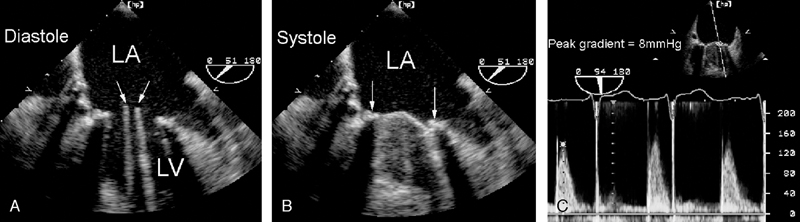

فحوصات تشخيصية لبعض امراض القلب والشرايين التاجية